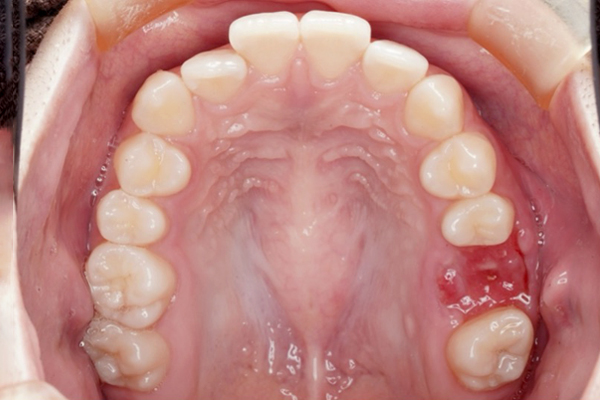

治療前(Before)

歯槽堤温存術の症例

⚫︎ 根の先端に大きな病変がある。

⚫︎ 治療を行って治癒する見込みが低い状態です。

⚫︎ 前後の歯は削りたくないので、今後インプラント治療を行なっていきます。